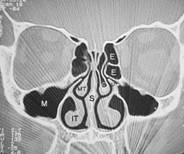

Was ist eine Nasenmuschel?Die unteren Nasenmuscheln befinden bds. in der Nase vom Eingang bis zum Ende der Nase, den sog. Choanen und sind an den seitlichen Nasenwänden knöchern abgewachsen. Sie vergrößern die Oberfläche der Nase um die Atemluft besser anwärmen, befeuchten oder reinigen zu können - sie sind also wichtig und man darf Sie nicht entfernen. Je nach Bedarf schwellen Sie an (noch größere Oberfläche) oder ab (kleinere Oberfläche). Das ist normal und wechselt physiologischerweise auch zwischen rechts und links ab. Dieses Abschwellen kann man z.B. auch mit den (auf Dauer benutzt schädlichen) abschwellenden Nasentropfen oder - sprays erreichen, die man rezeptfrei in der Apotheke kaufen kann. Dies sollte man aber nur bei akutem Schnupfen o. Ä. tun, auf Dauer wird die Nasenatmung dadurch schlechter und die empfindliche Nasenschleimhaut wird dadurch zerstört. Warum werden diese wichtigen Nasenmuscheln zu groß?Ist dieses Anschwellen allerdings, z.B. durch Klimaeinflüsse, Allergien, Staub- oder Toxinexposition extrem verstärkt und die Nasenmuscheln sind über Ihr Maß hinausgewachsen, dann hilft in manchen Fällen nur noch die chirurgische Verkleinerung - entweder durch "Stahl oder Strahl" - die Mediziner meinen damit eine Verkleinerung mittels chirurgischer Instrumente oder Laser. Es gibt auch noch andere Methoden, die ich nahezu alle schon persönlich angewendet habe. z.B. Radiofrequenz, Argon-Plasma-Koagulation, Cobalation usw. Wir haben uns in unserer Praxis für einen Diodenlaser entschieden - doch dazu später mehr. Wo genau sind diese Nasenmuscheln?Da man sich als Laie schlecht vorstellen kann wo genau diese Nasenmuscheln in der Nase sitzen hier zusätzlich zu dem oberen Bild ein frontaler Querschnitt durch das Mittelgesicht:

Erklärung: Schwarz: Luft, Graustufen: Weichteile, Weiß: Knochen, IT: untere Nasenmuschel, M: Kieferhöhle, S: Nasenscheidewand